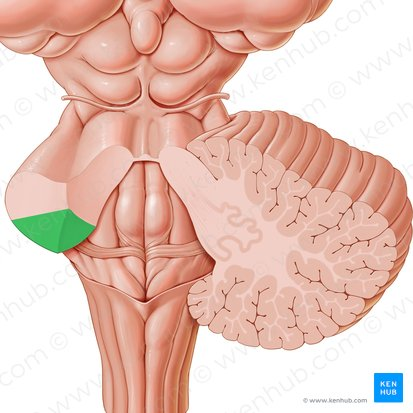

midbrain

green portion

pons

pink portion